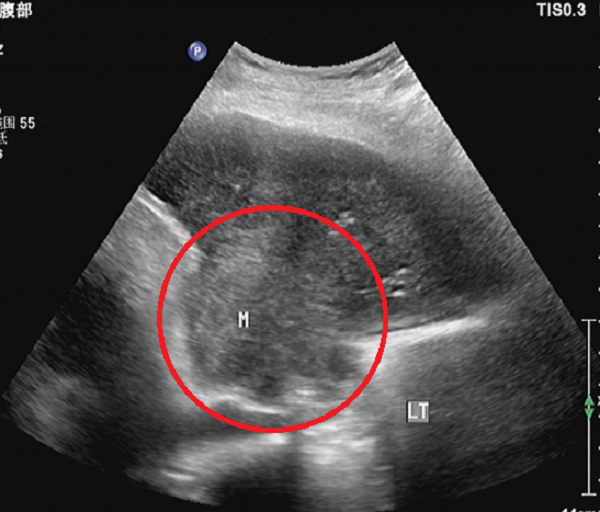

“肝脏小侦探”——我院开展新技术:肝脏弹性检测

随着影像技术的不断发展,我院健康管理科引进超声“新武器”,于2023年7月正式开展“肝脏瞬时弹性检测”。这项新技术真正实现了脂肪肝及肝纤维化的早期筛查、预防与诊断,为治疗方案的制定提供了精准的依据,给各类肝病患者带来了极大的福音。什么是肝脏瞬时弹性检测?它适应什么样的患者?注意事项又有哪些? 肝脏瞬时弹性检测(FibroScan)是一种新型的肝纤维化无创检测方式,通过测量肝脏硬 度来判断肝脏纤维化的程度,对肝纤...